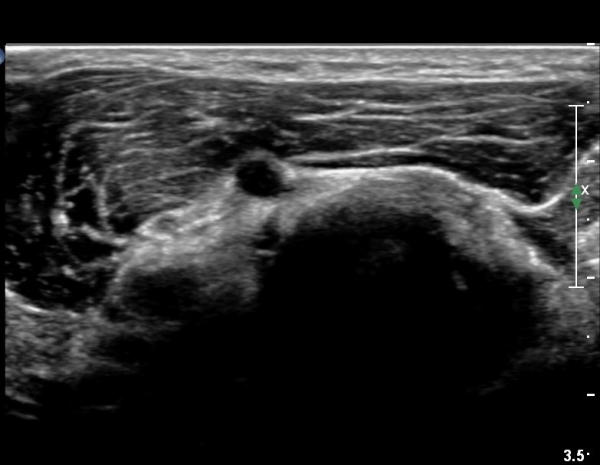

¿ä°ñµÎ ±ÙÀ§ºÎ Ⱦ´Ü¸é°Ë»ç»ó Èİñ°£ ½Å°æ ³»ÃøÀ¸·Î ÀÛÀº ³¶Á¾ÀÌ °üÂûµÈ´Ù(»çÁø 1).